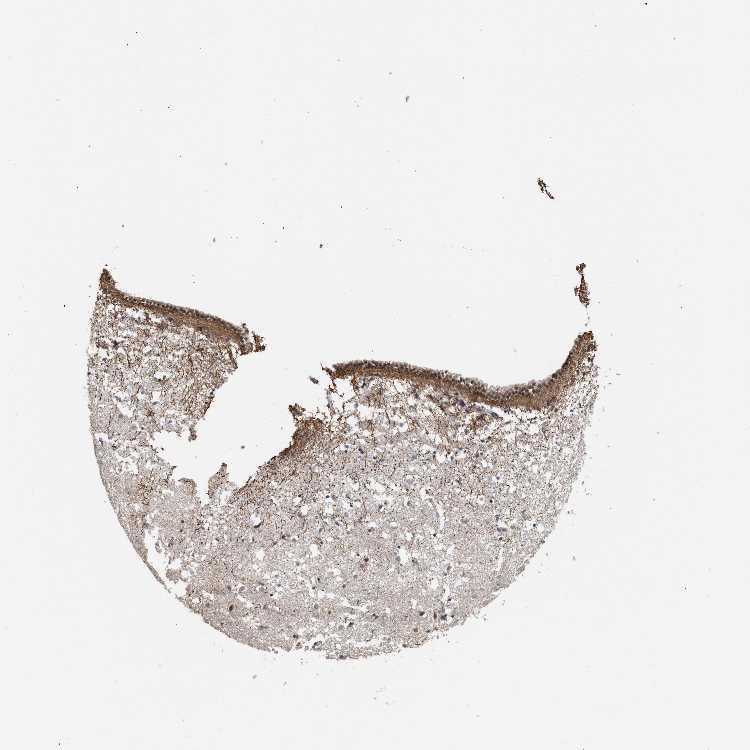

CAUDATE - Antibody stainingi

Antibody staining in the annotated cell types in the current human tissue is reported as not detected, low, medium, or high, based on conventional immunohistochemistry profiling in selected tissues. This score is based on the combination of the staining intensity and fraction of stained cells.

Each image is clickable and will lead to virtual microscopy that enables deeper exploration of all samples and also displays staining intensity scores, fraction scores and subcellular localization as well as patient and tissue information for each sample.

Antibody CAB019271

Glial cells Low

Neuronal cells Low